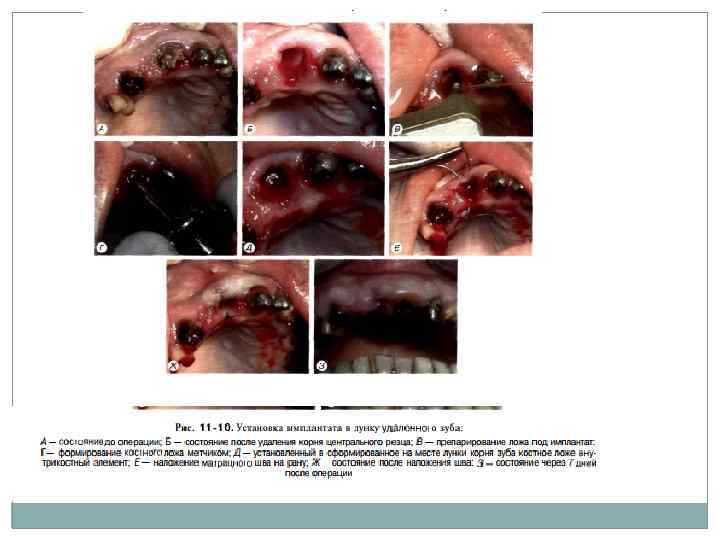

Установка имплантатов непосредственно в лунку удаленных зубов Для этой цели обычно используют двухэтапныс винтовые или цилиндрические имплан таты (рис. 11 10). Удаление зуба должно быть атравматнчным, без грубого повреждения краев лунки. После удаления производится частичное (препарирование направляющего канала в не которых случаях не требуется) препарирование костного ложа соответствующими инструмен тами для достижения конгруэнтности поверх ностей лупки и имплантата. а также первичной фиксации имплантата. В том случае, когда посте препарирования ложа удалось обеспечить кон груэнтность поверхностей лунки и имплантата, осуществляют его установку: адаптируют и мобилизуют слизистую оболочку краев лунки; рану зашивают. В ряде случаев после установки имплантата образуется зазор между стенкой лунок и им плантатом. Образовавшийся зазор необходимо заполнить оетеокондуктивным и/или остео индуктивным материалом: при необходимости обеспечить его изоляцию с помощью барьерной мембраны: осуществить мобилизацию краев раны и зашить ее.